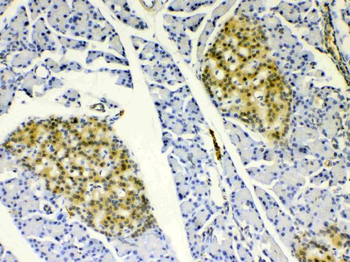

10 μg, 100 μg - Anti-Hsp90 alpha/HSP90AA1 Antibody [orb196259]

FC, ICC, IF, IHC, WB

Human, Mouse, Rat

Rabbit

Polyclonal

Unconjugated

10 μg, 100 μg - Anti-DR5/TNFRSF10B Antibody [orb389514]